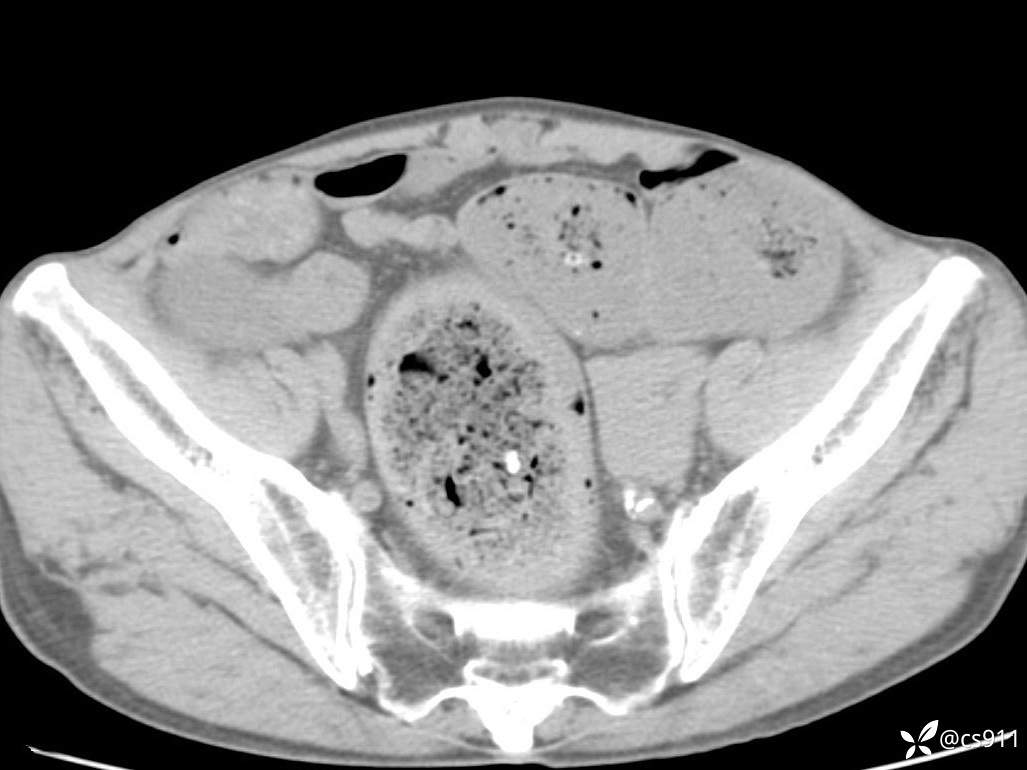

急腹症之急诊CT,原因?答案公布

男,77岁,腹痛、腹胀伴恶心呕吐1天。呕吐胃内容物,非喷射性呕吐,有咖啡色样胃内容物,诉有胃穿孔病史。查体:全腹平,下腹部压痛,全腹无反跳痛,叩诊呈浊音,移动性浊音阴性,肠鸣音减弱,1-2次/分。肛检:直肠未扪及明显肿物,可触及大量粪块。

血淀粉酶(AMY) HH 1859 U/L 35-135

癌胚抗原(CEA) H 27.44 ng/ml 0-5